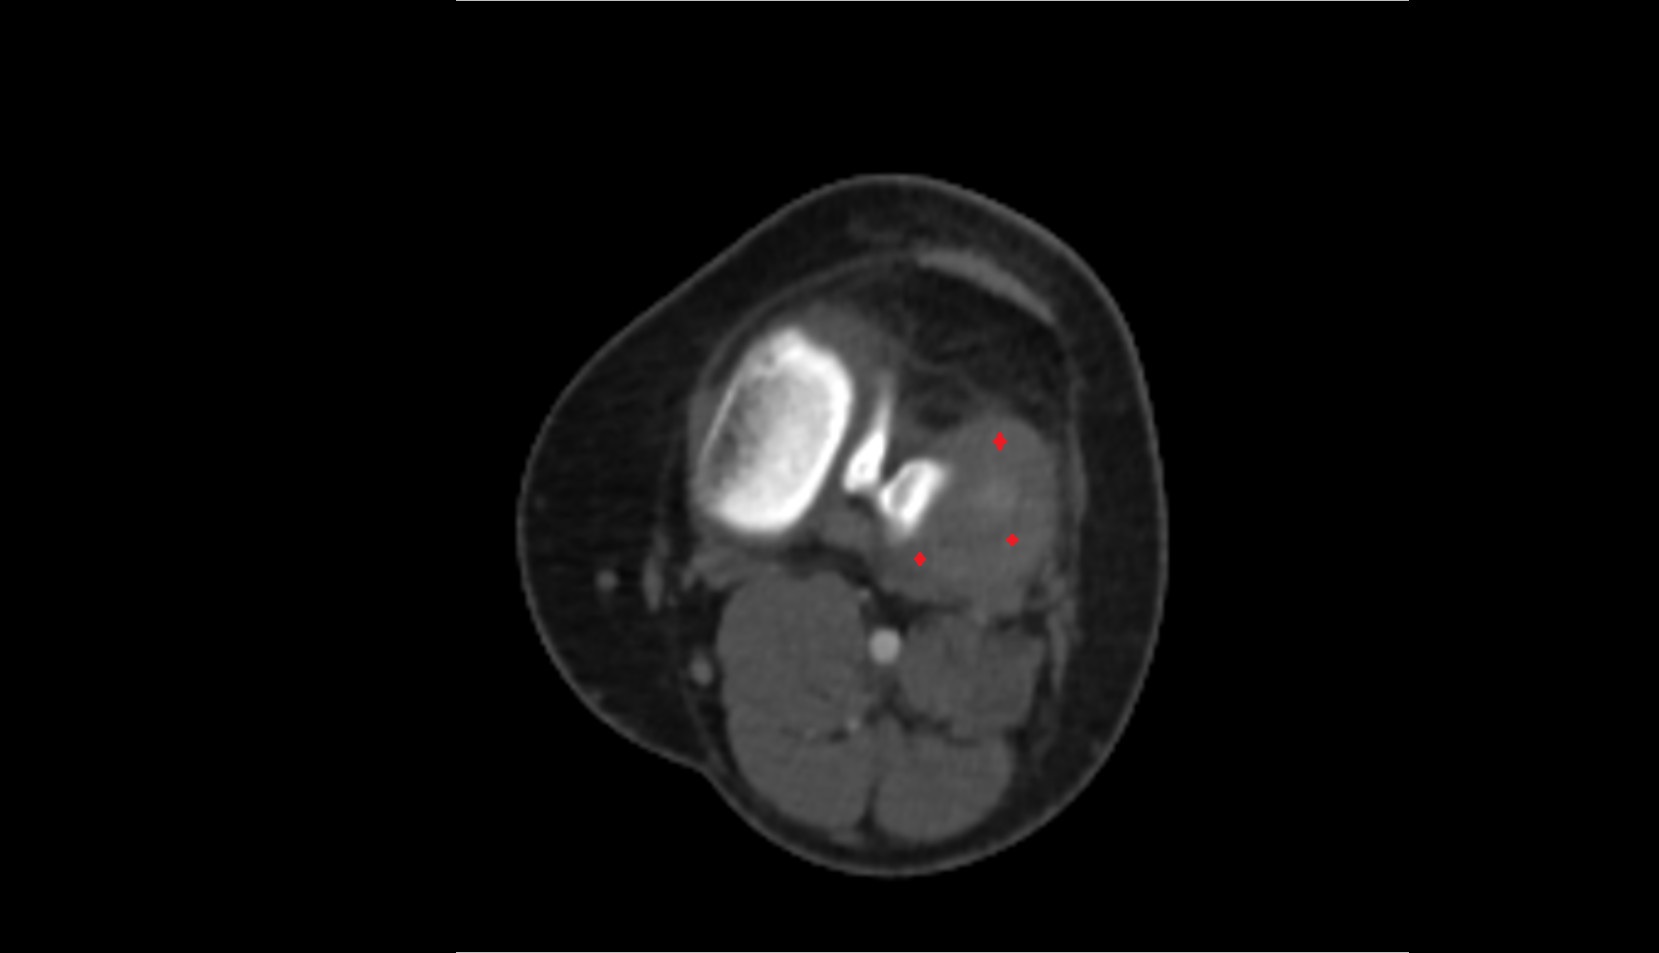

- Knee Joint

- Anterior cruciate ligament

- Posterior cruciate ligament

- Popliteal artery

- Popliteal vein